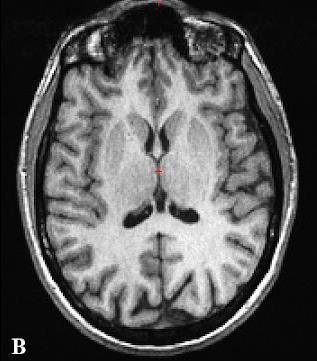

SISMIK le modèle de correction

Nous proposons un système de correction de mouvement rétrospectif sur les données de mesure IRM (espace-K) appelé SISMIK qui reconstruit des images avec moins d’artéfacts de mouvements.

Le système est dit hybride entre l’intelligence artificielle et les méthode algorithmiques plus traditionnelles, combinant les avantages des deux approches.

1. Les mesures “brutes” sont montrées à un réseau de neurones convolutionnel (CNN) entraîné au préalable.

2. le CNN estime pour chaque ligne d’aquisition le déplacement relatif effectué par rapport au lignes adjacentes.

3. le réseau produit une trajectoire complètes (mouvement dans le temps) le long de l’acquisition

4. la trajectoire et les données brutes sont envoyées au second algorithme afin qu’il corrige et reconstruise les images correspondantes.

Notre méthode est dite rétrospective (appliquée après la mesure) et basée sur la technique IRM exclusivement. Ses avantages sont les suivants:

▪ Aucune modification des séquences cliniques usuelles (des modifications rendraient les séquences non-standard et nécessitent un développement et une validation spécifique pour chaque constructeur/marque IRM).

▪ Pas de séquence additionelle nécessaire, la référence du mouvement est relative et contenue dans l’acquisition

▪ Aucun équipement supplémentaire ou externe est nécessaire.